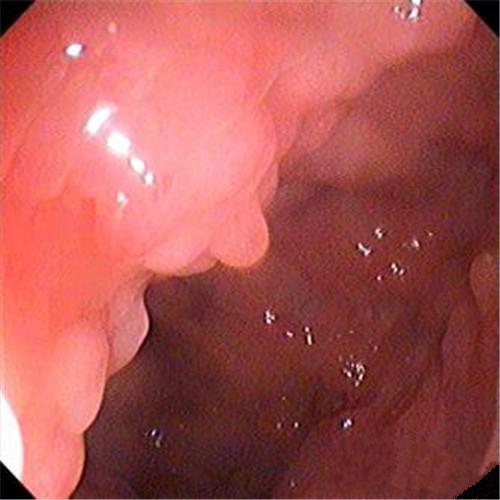

潰瘍性結腸炎圖片

潰瘍性結腸炎乳頭狀